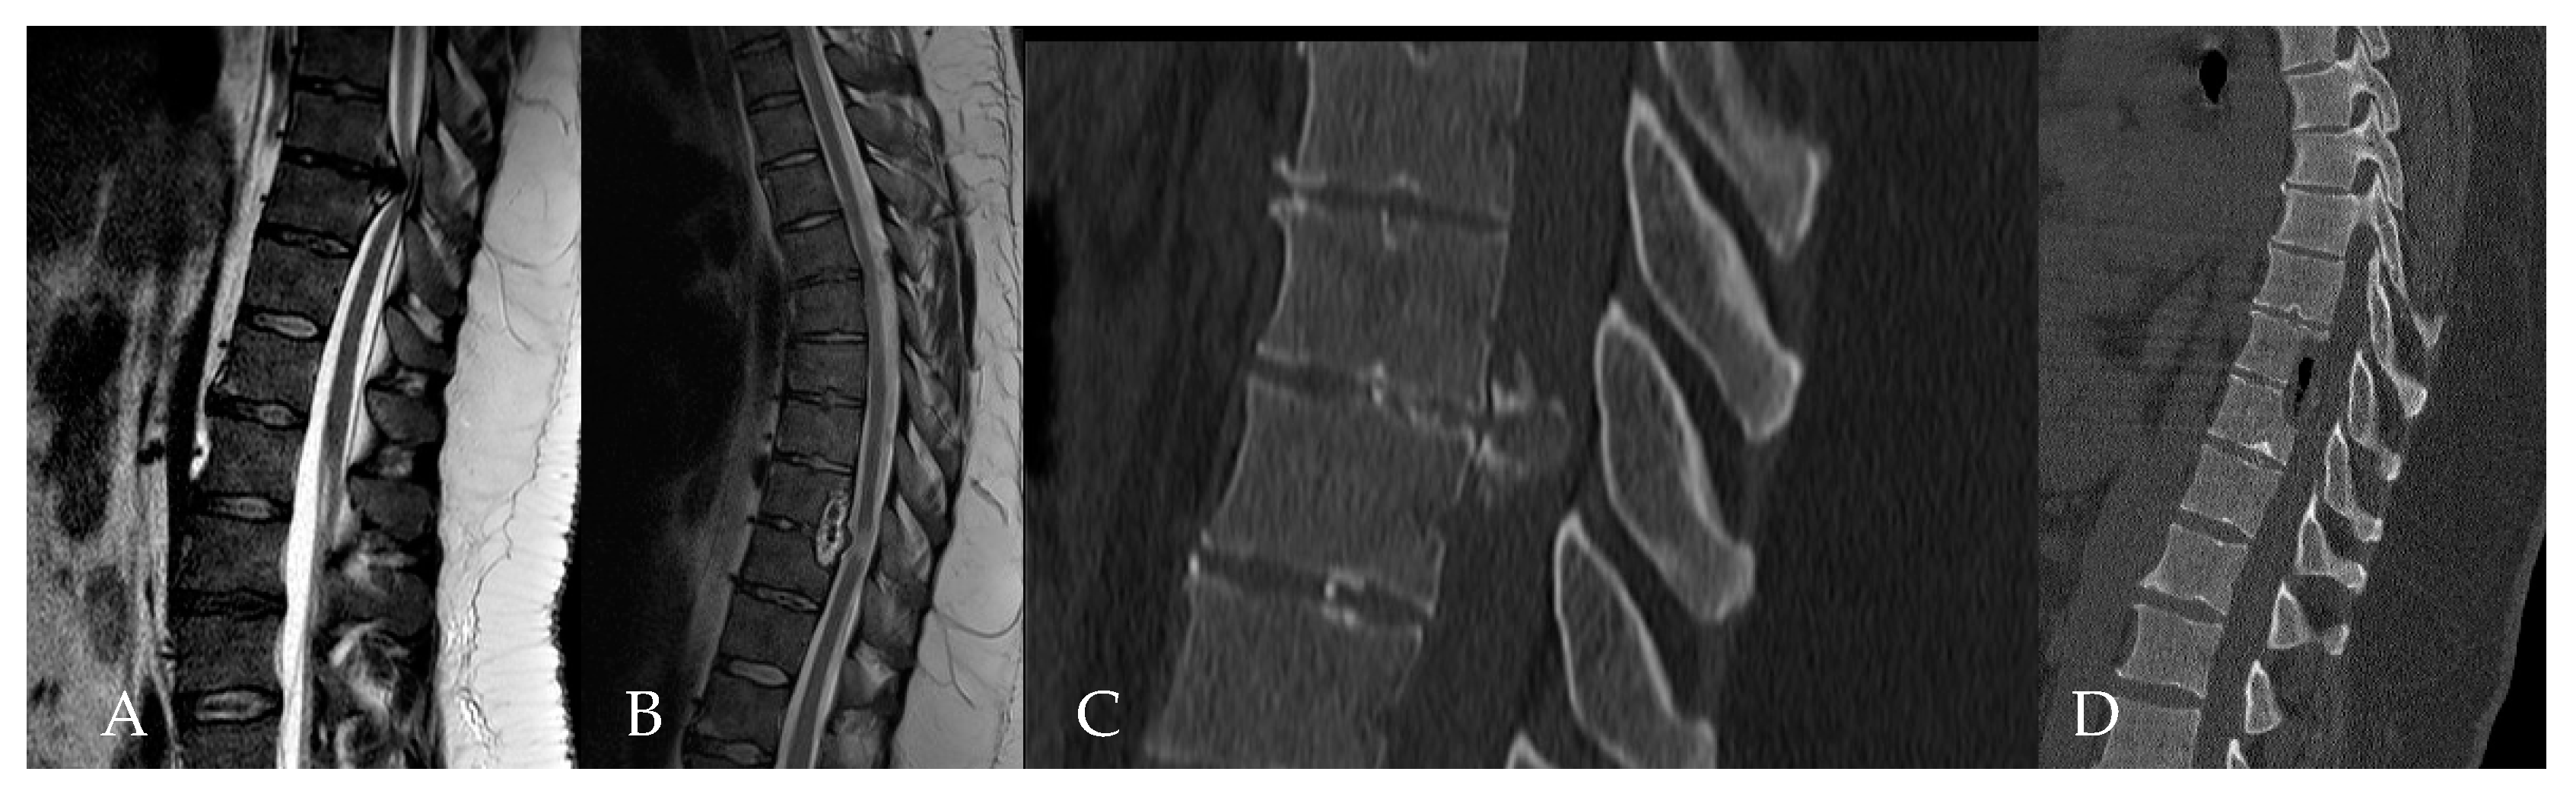

4. Patients